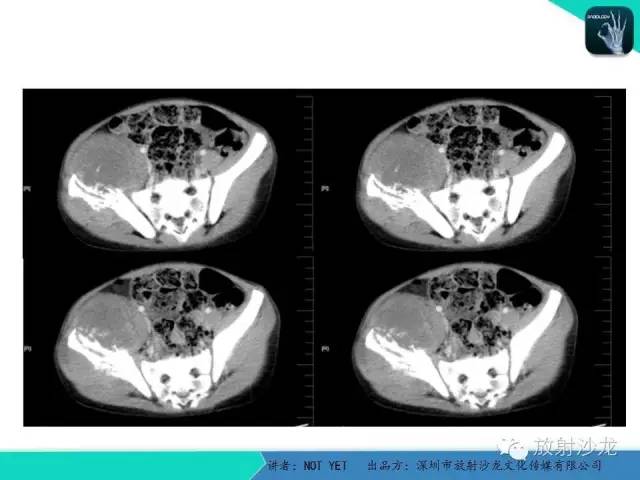

【病例】右侧髂骨Ewing肉瘤1例CT影像表现